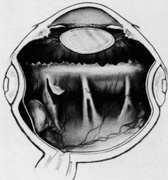

After the suprachoroidal space is entered, diathermy can be used to shrink the margins of sclerotomy to improve choroidal exposure. The choroid then is inspected under magnification for choroidal vessels. If major choroidal vessels are seen, consideration is given to selecting another drainage site if possible. The choroid is diathermized to decrease the chance of bleeding on entry. The diathermy shrinks the choroid and closes choroidal vessels. Under magnification, diathermy can be seen to change the normal smooth, dark blue color of the choroid to a parchment gray color and texture (Fig. 29).

Fig. 29. A. Location of scleral cutdown in bed of buckle. B. Diathermy of scleral margin. C. Diathermy of choroid.